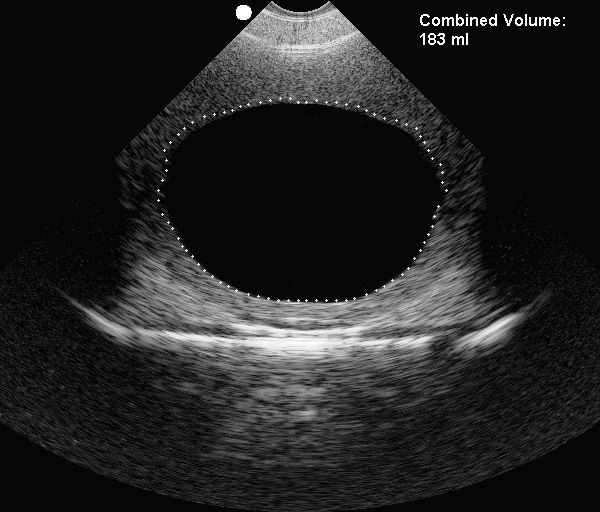

CUBEScan BioCon700S Bladder Scanner Accurate bladder volume results

A LowCost, Durable and ReUsable Bladder Phantom Teaching Bladder Scanner Calibration Phantom set up & maintain the string phantom the string phantom is used for aligning probes and testing proper probe function. calibration kit • calibrate any biocon 700 scanner onsite, as frequently as needed • only one calibration kit is needed, even for multiple scanners • no internet. ® • if you are a new bladderscan user, verathon recommends. Bladder Scanner Calibration Phantom.